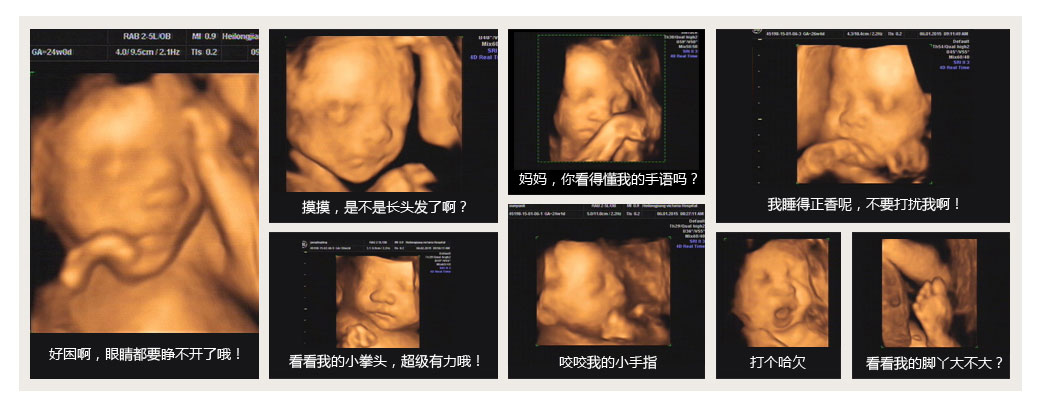

此时是做四维彩超的时间,这个时期胎儿局部结构及运动状态比较清晰,成像效果也比较好,可及时发现严重的胎儿畸形,诊断胎儿结构异常的准确率可达到95%-987%